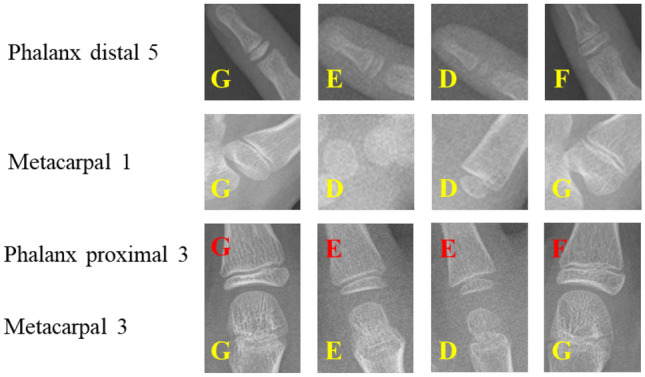

Examples of stage determination are shown in the Fig. 11. On the evaluation split of Private dataset 1, we calculate the cumulative score to analyze each model belonging to each specific bone:

Fig. 11.

Examples of stage determination